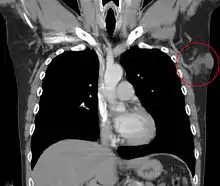

Metastases to regional lymph nodes are extremely rare.[37] Distant hematogenous metastases are even rarer and are most likely in patients who have had multiple local recurrences after inadequate surgical resection.[38] Repeatedly recurring tumors have an increased risk for transformation into a more malignant form (DFSP-FS). The lungs are most frequently affected, but metastases to the brain,[39] bone,[40] and other soft tissues are reported.